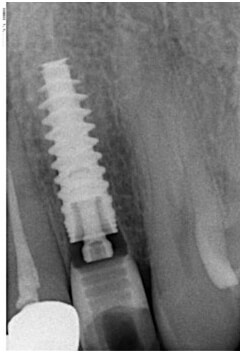

İmplantın başarılı yerleştirilmesi için, implant ile komşu diş arasında, hem diş hem de interproksimal kemik için yeterli yer olmalıdır. En dar implant, shoulder veya platformda 4 mm genişliğindedir. Düzenli iyileşmeye izin vermek ve papillaya uygun yer sağlamak için implant ile komşu diş arasında yaklaşık olarak 1 mm olmalıdır, bu yüzden en az boşluk 6 mm.dir. Boşluk sadece sırtın kretinde değil, komşu dişlerin kökleri arasında da olmalıdır. İmplantın cerrahiyle köke ve apikal dokulara zarar vermeden cerrahisine izin vermesi için, komşu dişlerin apeksleri yeterince uzak olmalıdır.

Ortodonti Tekniği. Genel olarak, gereken yerin elde edilmesi için plan yapıldıysa ve istenen kök pozisyonlaması yapıldıysa, mekanikler benzerdir ve dikkatli braket yerleşimi ve ankraj kontrolü gerekir. Kron tipinginden daha yavaş oluşan kök hareketi, tedavinin süresini belirleyecektir. İdeal kök yerleşimi sağlamak 6 ay sürer. Ortodontik apareylerin hareketine göre dişlerin angulasyonunu periapikal radyograflarla pekiştirmek iyi bir pratiktir.

Kemik miktarı implantın başarısını direk etkiler. O yüzden implant yeri açmak için ortodontik tedavi kısa tutulmamalı ara periapikal röntgenlerle yer durumu sık sık kontrol edilmelidir. Komşu dişlerde kök paralelliği sağlanmalıdır. Yer durumunun kritik olduğu anterior bölgelerde diş çekimli ortodontik tedaviler ve son aşamada çaresiz kalınırsa zirkonyum protezler bile tedavi alternatifleri arasına alınmalıdır.